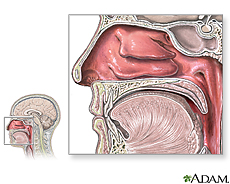

Your nose is important to your health. It filters the air you breathe, removing dust, germs, and irritants. It warms and moistens the air to keep your lungs and tubes that lead to them from drying out. Your nose also contains the nerve cells that help your sense of smell. When there is a problem with your nose, your whole body can suffer. For example, the stuffy nose of the common cold can make it hard for you to breathe, sleep, or get comfortable.

Many problems besides the common cold can affect the nose. They include

- Deviated septum – a shifting of the wall that divides the nasal cavity into halves

- Nasal polyps – soft growths that develop on the lining of your nose or sinuses

- Rhinitis – inflammation of the nose and sinuses sometimes caused by allergies. The main symptom is a runny nose.